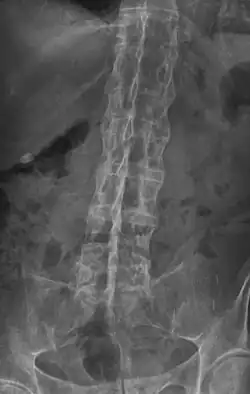

„Bambusstab“-Wirbelsäule im Röntgenbild

Erosion, reaktive Verkalkungen, und Verknöcherung der Articulatio sacro-iliaca waren seit den 1930er Jahren die ersten pathognomonische Symptome der Spondylitis ankylosans. In späteren Stadien kann es zu Knochenspangen zwischen benachbarten Wirbeln und Verknöcherungen des Wirbelkörperbandapparates kommen. Die Verknöcherung der Wirbelsäule ist auf Röntgenbildern gut zu erkennen und wird wegen ihrer markanten Form auch als Bambuswirbelsäule bezeichnet.